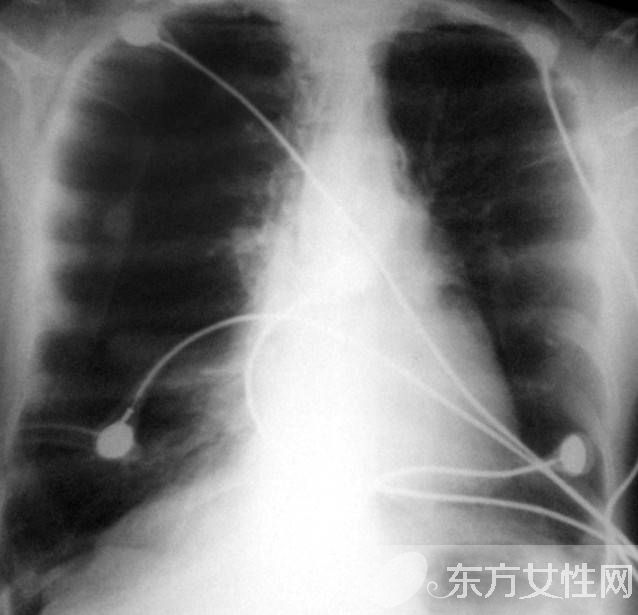

在正常的呼吸中,肺泡扩张后收缩,使氧气进入血液,并且把二氧化碳排出。患上肺气肿之后,肺泡失去弹性,为了代替,就过度扩张,以致破裂,因而减少了氧气的摄入量。这样一来,心脏及颈、胸、腹部与呼吸有关或控制呼吸的肌肉必须更加用力地工作,以便摄取足够氧气。此外,患者的两肺膨大,从侧面看上去有桶状胸。肺气肿病情进至严重阶段,患者持续缺氧,同时过量的二氧化碳积聚在体内。患者须要借助医疗措施来改善呼吸,包括使用机械辅助呼吸与面罩吸氧。最后,患者的呼吸功能可能完全衰竭。

轻度肺气肿体征多无异常。肺气肿加重时胸廓前后径增大,外观呈桶状,脊柱后凸,肩和锁骨上抬,肋间隙饱满,肋骨和锁骨活动减弱。语颤减弱,叩诊呈过清音,心浊音界缩小或消失,肝浊音界下降。呼吸音及语颤均减弱,呼气延长。有时肺底可闻及干湿啰音,心音遥远,肺动脉第二心音亢进。重度肺气肿患者,即使在静息时,也会出现呼吸浅快,几乎听不到呼吸音。可出现发绀,合并肺心病右心衰竭时可出现颈静脉怒张、腹水、肝大,凹陷性水肿等体征。